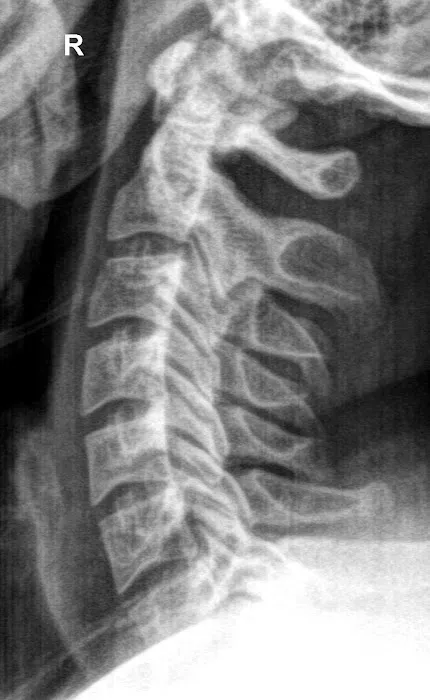

- Diagnostic X-rays: Equipped with an in-house X-ray suite for precise diagnosis, allowing Dr. J to see underlying problems and develop effective treatment plans.

- Comprehensive Diagnostic and Treatment Capabilities: With in-house X-rays, various adjusting techniques, and complementary therapies like acupuncture and myofascial work, Adjusted Health offers a thorough approach to patient care.